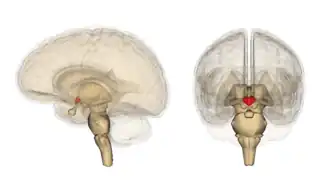

Местоположение гипоталамуса в мозге

Гипотала́мус[1] (лат. hypothalamus, от др.-греч. ὑπό ‘под’ и θάλαμος ‘комната, камера, отсек, таламус) — небольшая область в промежуточном мозге, включающая в себя большое число групп клеток (свыше 30 ядер)[2], которые регулируют нейроэндокринную деятельность мозга и гомеостаз организма. Гипоталамус связан нервными путями практически со всеми отделами центральной нервной системы, включая кору, гиппокамп, миндалину, мозжечок, ствол мозга и спинной мозг. Вместе с гипофизом гипоталамус образует гипоталамо-гипофизарную систему, в которой гипоталамус управляет выделением гормонов гипофиза и является центральным связующим звеном между нервной и эндокринной системами. Он выделяет гормоны и нейропептиды и регулирует такие функции, как ощущение голода и жажды, терморегуляция организма, половое поведение, сон и бодрствование (циркадные ритмы). Исследования последних лет показывают, что гипоталамус играет важную роль и в регуляции высших функций, таких как память и эмоциональное состояние, и тем самым участвует в формировании различных аспектов поведения.

Гипоталамус является частью промежуточного мозга. Он образует основание и стенки нижней части третьего желудочка. Название своё он получил от греч. гипо- (под, внизу) и таламос (чертог, спальня), так как он располагается под таламусом. Гипоталамус отделён от таламуса гипоталамической бороздой (лат. sulcus hypothalamicus). Анатомические границы гипоталамуса определены недостаточно чётко, что связано с тем, что некоторые группы клеток заходят в соседние области, а также с некоторой неопределённостью в терминологии[3]. Считается, что спереди (рострально) гипоталамус ограничен терминальной пластинкой (лат. lamina terminalis), а его задняя (каудальная) граница — воображаемая линия от задней комиссуры (лат. commissura posterior) до каудальной поверхности сосцевидных тел. Дорсолатерально гипоталамус доходит до медиального края мозолистого тела[4].